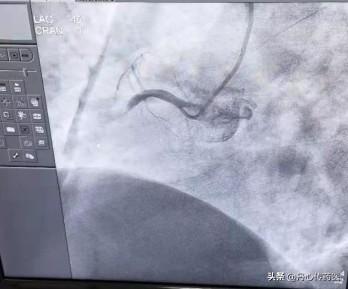

Qu'en est-il de cette artère coronaire ? Commençons par une image.

Les flèches pointent vers les artères coronaires, dont le rôle est d'alimenter notre cœur en sang. Pour utiliser une analogie plus graphique, notre cœur est un terrain, les artères coronaires sont les canaux, et notre muscle cardiaque a pour rôle de faire pousser les cultures. Si nos canaux sont bloqués, alors. Nos récoltes mourront. La nécrose myocardique est la cause de la mort des cultures dans notre cœur. Vous pouvez penser à ce que fait le muscle cardiaque, le muscle cardiaque est notre pompe à sang, si le muscle cardiaque n'est pas fort, alors notre corps ne peut pas avoir assez de nutriments. Par conséquent, après l'obstruction de l'artère coronaire, le muscle cardiaque mourra, et cette nécrose est appelée infarctus. Il s'agit de l'infarctus du myocarde.